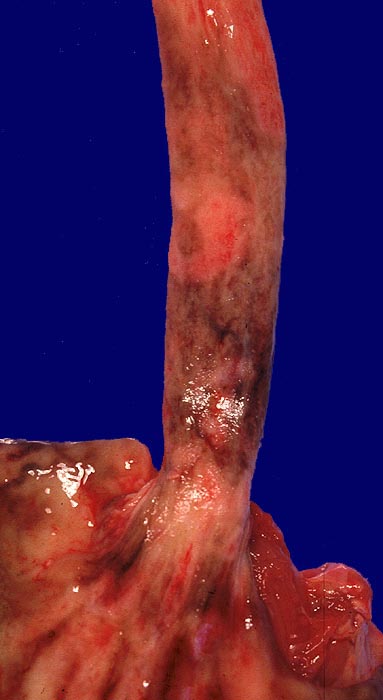

Erosion bei Soorösophagitis

Multiple konfluierende braun verfärbte Erosionen der Ösophagusschleimhaut.

Soor mikroskopisch im Bereich der Erosion. Alkoholische Leberzirrhose.